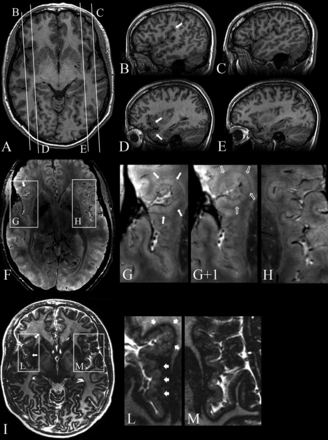

Patients 1 (A and B) and 9 (C and D). Comparison of 3T axial 3D FSPGR (A) and 7T axial 3D SWAN (B) images. Contiguous 7T axial 3D SWAN acquisitions show anatomic details of the polymicrogyric cortex (C and D). A, Delicate appearance of the polymicrogyric cortex in the left pre- and postcentral sulci, characterized by multiple small and delicate gyri of thin cortex (arrow). B, A thin and undulated polymicrogyric cortex, in which the spaces between microgyri are filled by thin white matter digitations, which have a low periodicity and are loosely packed. The gray-white matter junction is bordered by a thin hypointense line. 7T can, therefore, resolve the individual microgyri, revealing how grossly different morphologic characters (coarse or delicate) at 3T result, in fact, from variations of a common underlying morphologic pattern. B, Examples of cortical thickness measurements of normal (2.23 mm) and polymicrogyric cortex (1.13–5.22 mm) by using the straight-line distance measure between the surface and depth of the cortex. C and D, SWAN images show details of cortical structures and allow disentanglement of the structural units underlying the radiologic appearance of polymicrogyria. The typical undulated aspect is clearly detectable following the hypointense lines of the cortical border (arrowheads), which we assume represent arcuate white matter fibers, the white matter digitations within the gyri (arrows), the small vessels joining the pial veins (asterisks), and the fused molecular layer (crosses).

The increased signal-to-noise ratio and the increased sensitivity to magnetic susceptibility effects on SWAN sequences at 7T combined with high-resolution images with enhanced intracortical contrast provided improved polymicrogyria detailing by making it possible to identify details in the entire cortex: the lowest part of the sulcus, the intermediate zone, and the crown of the gyrus. The different categories of gyral and sulcal dysmorphisms seen at 3T (coarse, delicate, sawtooth) were not identifiable as such at 7T, in that SWAN images revealed a homogeneous morphologic character (Fig 2B and On-line Fig 1B). The malformed cortex, measured by using SWAN imaging, was 0.78- to 7-mm thick (the normal cortex was 1–2.89 mm), exhibiting an undulated profile at the gray-white matter junction and bordered by a thin hypointense line, which was considered to represent the arcuate white matter fibers. Within the abnormal cortex, small linear hypointense transcortical lines perpendicular to the cortical layers, probably representing the larger transcortical blood vessels, were present. The hypointense lines of the cortical border combined with those within the cortex contributed to generating the typical polymicrogyric appearance of the cortical ribbon at 7T (Fig 2C, -D).